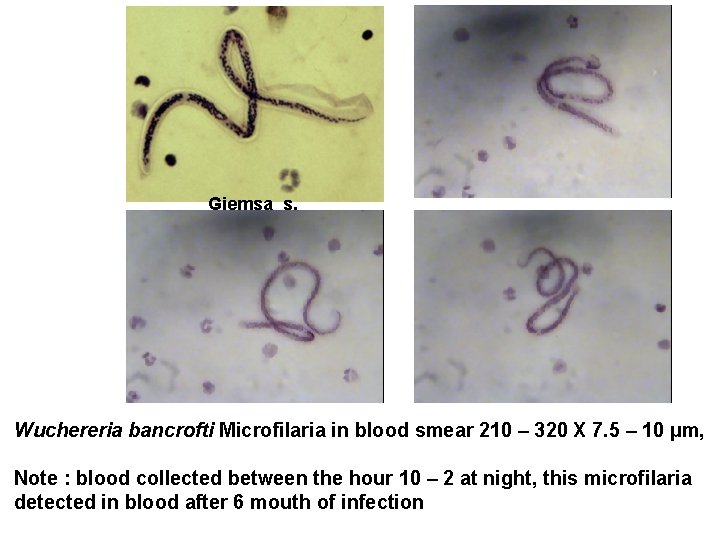

Giemsa s. Wuchereria bancrofti Microfilaria in blood smear 210 – 320 X 7. 5 – 10 µm, Note : blood collected between the hour 10 – 2 at night, this microfilaria detected in blood after 6 mouth of infection